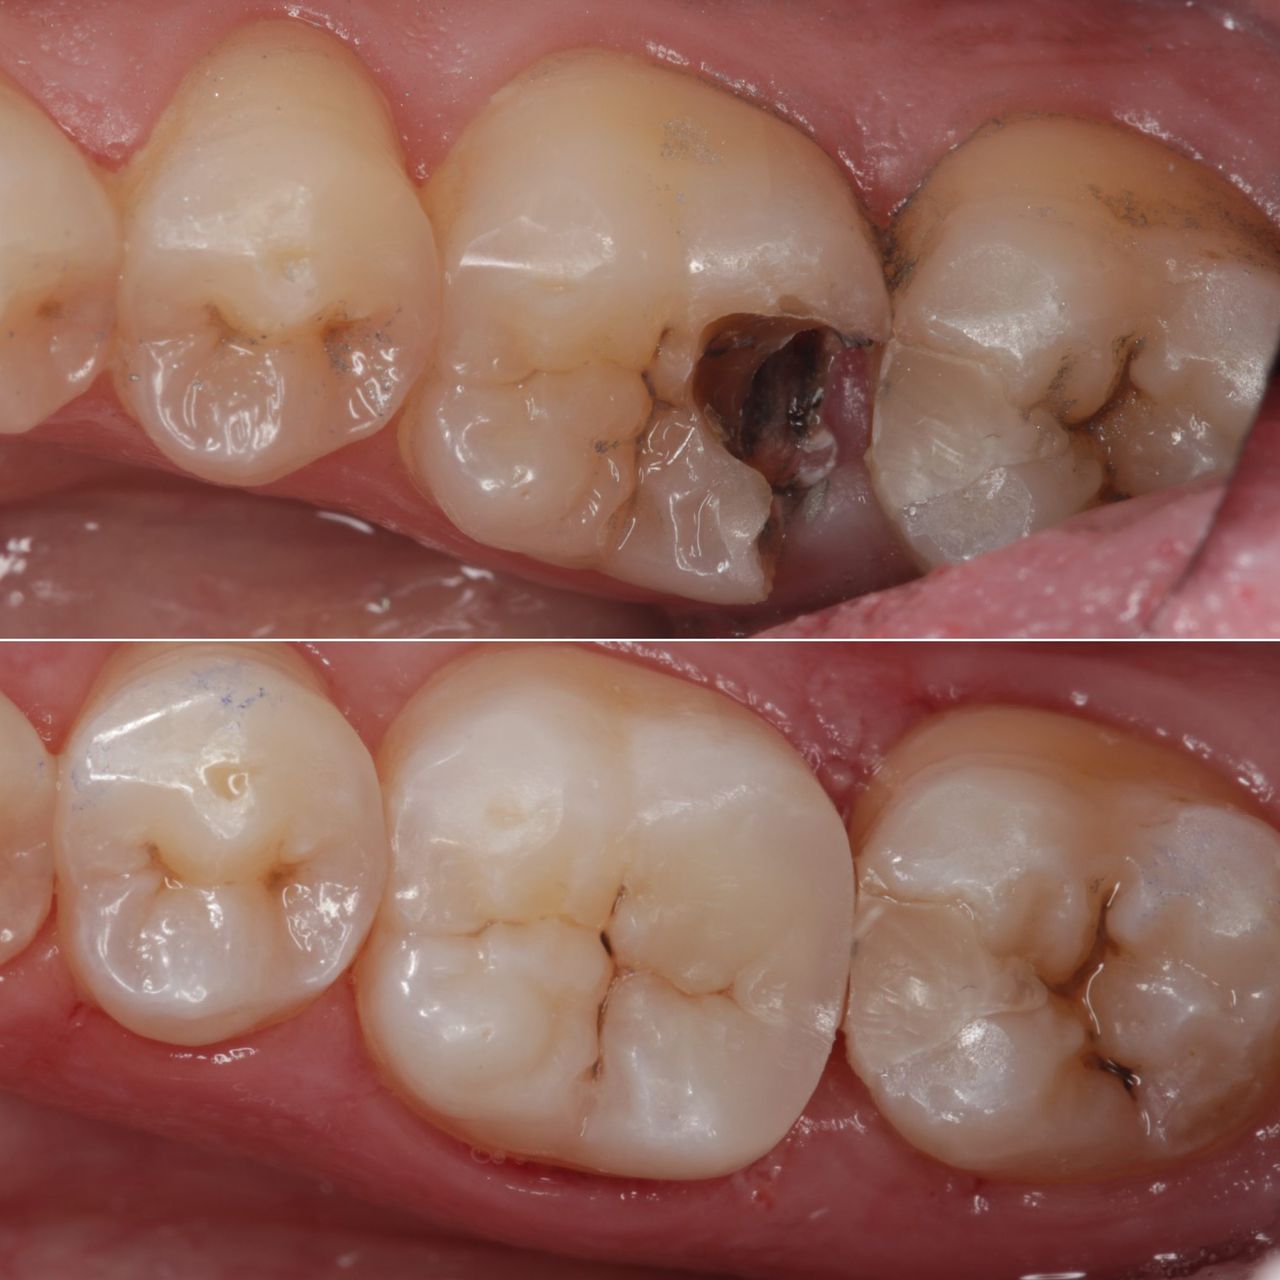

Dr Valeriia w 2015 ukończyła Uniwersytet Medyczny na kierunku Stomatologia w Charkowie, od kilku lat mieszka w Polsce, a posługując się płynnym językiem polskim, ukraińskim, rosyjskim i angielskim oraz prezentując światową jakość swojej pracy bardzo szybko zdobyła zaufanie i sympatię pacjentów. Doświadczony endodonta - większość kierowanych do niej przypadków zębów skazanych na usunięcie jest w stanie uratować leczeniem kanałowym. Znana z wybitnie estetycznych i biomimetycznych wypełnień kompozytowych. Jej prace to przykład doskonałej odbudowy zęba, zarówno pod kątem funkcjonalnym jak i estetycznym.

Od początku swojej drogi zawodowej związana była z jedną z najnowocześniejszych klinik, gdzie uczyła się od wybitnych specjalistów z branży. Swoją praktykę lekarską rozpoczęła zajmując się endodoncją, zdobyła w tej dziedzinie ogromne doświadczenie. Zajmuje się wykonywaniem najbardziej zaawansowanych leczeń endodontycznych, powtórnych leczeń kanałowych oraz usuwaniem złamanych narzędzi i zamykaniem perforacji.

Pracuje zawsze pod mikroskopem, w osłonie koferdamu i zawsze w oparciu o tomografię komputerową, w klinice posiada najnowocześniejszy sprzęt tomograficzny oraz narzędzia maszynowe do leczeń kanałowych.

Jej pasją jest leczenie zachowawcze, wypełnienia z jej ręki są małymi dziełami sztuki, idealnie i anatomicznie wykończonymi. Precyzja i cierpliwość w sposobie pracy w połączeniu z wysokim poczuciem estetyki umożliwiły tej naturalny rozwój w kierunku stomatologii estetycznej. Dr Valeriia wykonuje precyzyjne kompozytowe odbudowy zębów przednich, bondingi oraz prace „z ręki”.

Doktor uważa, że obraz mówi więcej niż słowa, zapraszamy do zapoznania się z galerią jej prac.